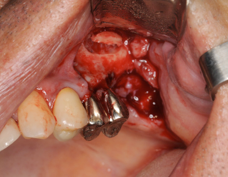

サイナスリフトとインプラント同時埋入しています。この場合だいたい9か月ほど

インプラントが骨に結合するまで待ちます

CTで人工骨がインプラントの周りに入っているのを確認しています。

サイナスリフトをする場合、CTがないと成功しているかの確認が難しいと思われます。